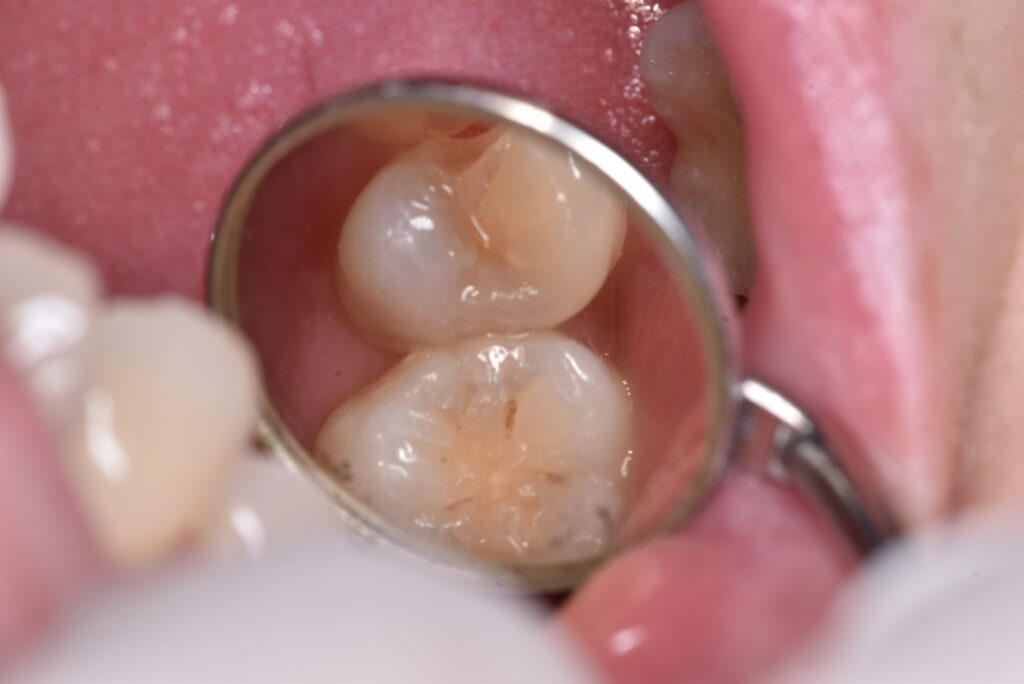

写真を見ていきましょう。実際に処置を行った時の写真です。下の写真は処置前のものになります。

間の部分にむし歯があるのですが、おわかりでしょうか?「なにもないよ!」と言う方の方が多いのではないでしょうか?では、ここを削っていったらどうなったのか、下の写真をご覧ください。